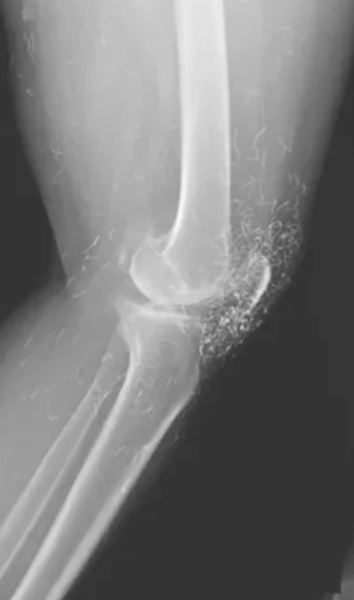

Дама, у которой диагностировали остеоартрит, лечила свои коленные суставы иглоукалыванием золотой нитью. Считается, что введение стерильных кусочков золота внутрь тела приводит к постоянной стимуляции и облегчению боли, но пациентке становилось только хуже. Когда же она наконец бросила иглоукалывание и обратилась в клинику, врачи обнаружили сотни крошечных золотых нитей, вросших в ткани вокруг колена.

Доктора давно уже предупреждали людей о том, что нет доказательств эффективности иглоукалывания золотыми нитями, но зато теперь имеется доказательство опасности такого лечения. К сожалению, дальнейшая судьба «золотой» пациентки неизвестна.